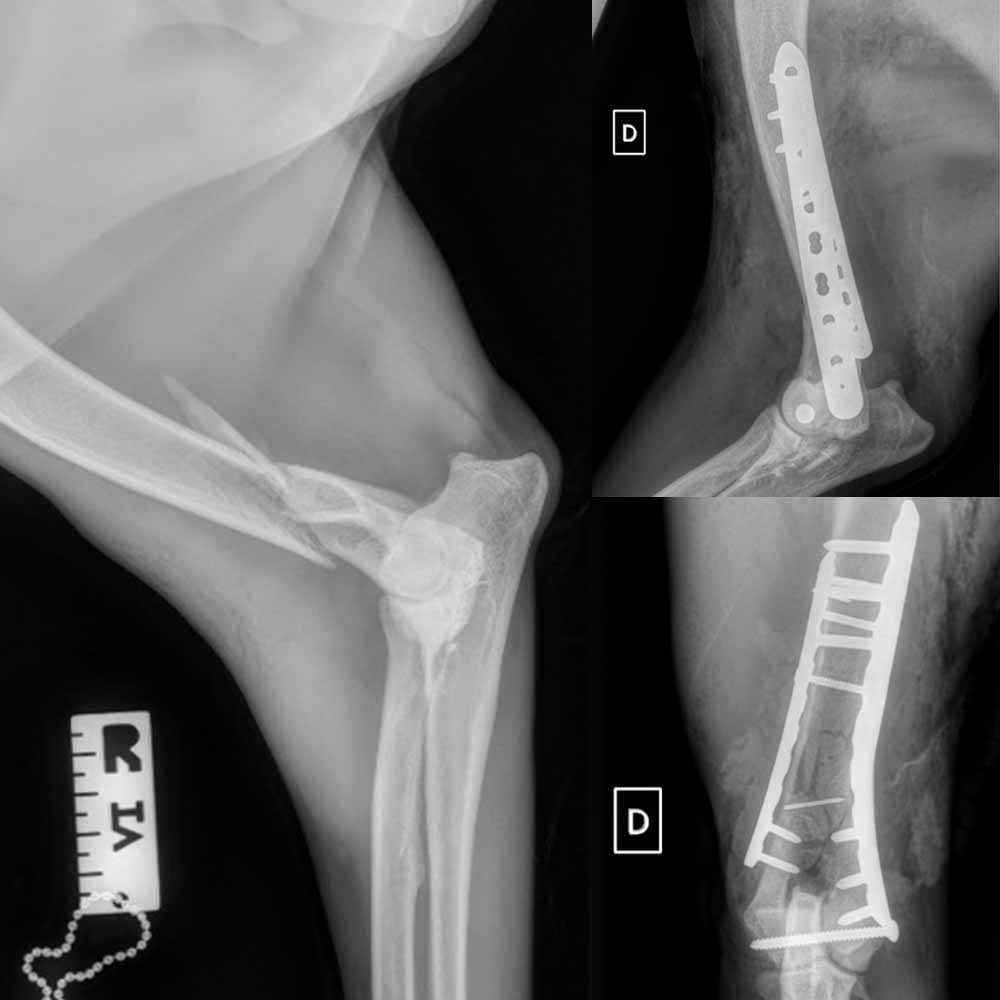

FAQ Chirurgie

Votre animal est référé au service de chirurgie d'AzurVet soit en vue d'un diagnostic, soit d'un traitement chirurgical (chirurgie orthopédique ou des tissus mous).

1) Votre animal est d'abord examiné par un chirurgien spécialiste diplômé d'un collège européen de chirurgie (ECVS). Des hypothèses diagnostiques sont alors discutées avec vous et un plan est décidé.

2) Le chirurgien transfère alors éventuellement le cas au service d'imagerie pour établir un diagnostic grâce à une échographie, un scanner, une IRM.

3) Une fois le diagnostic établi, un plan de traitement est discuté avec vous et les options médicales et/ou chirurgicales vous sont proposées ainsi qu'un devis précis.

4) Votre décision actée, l'animal est alors pris en charge pour sa chirurgie puis hospitalisé pour les soins post opératoires. Vous recevez un appel de notre part deux fois par jour (matin et soir) pour vous donner des nouvelles. Des visites sont parfois organisées en cas d'hospitalisation longue durée à l'initiative du chirurgien ou de ses assistants de chirurgie.